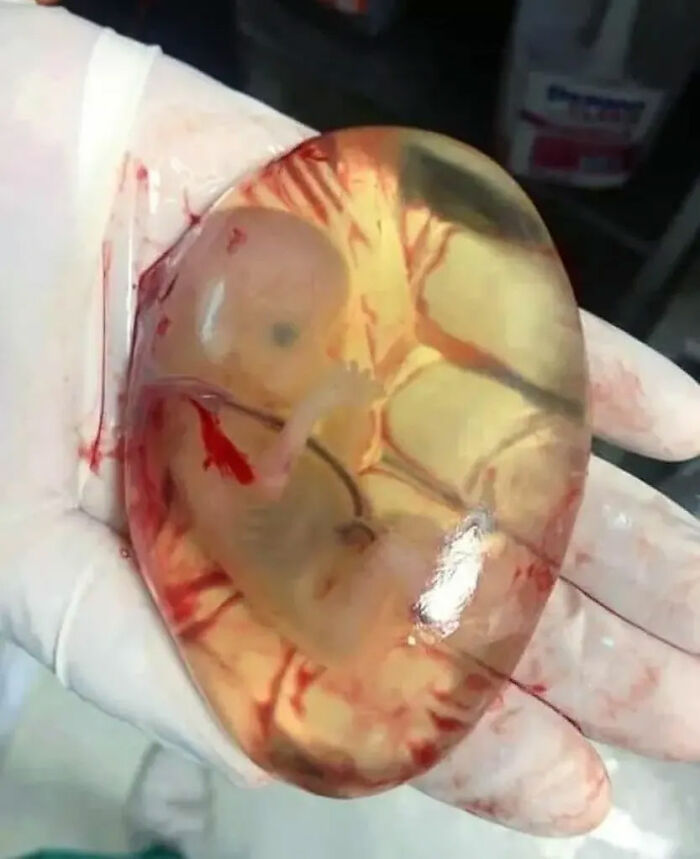

An En-Caul Birth On The Road!! Here’s An Incredible Birth Story Of A Baby Born Still Enclosed Within The Amniotic Sac

“The human body is truly an amazing thing. 8.5.2017 at about 10am I started having contractions. I was only 29 weeks and 4 days so I just figured they were Braxton hicks and decided to wait it out. After about 45 minutes of consistent contractions that were increasing in intensity I decided I should probably go in. I there in some clothes. Grabbed my daughter some clothes, her my fiance And I left for the hospital. I dropped my daughter to her God mommy Nicole And headed to the hospital. Well the contractions continued to get closer together and more intense and before I knew it I knew it was time to push. I called 911 because I was so scared. They couldn’t understand me between the screams with contractions. So I handed the phone to my fiance.

I pulled my pants off and reached down, sure enough his head was right there. I pushed one time and my miracle baby was here. When I looked down I realized he was still completely wrapped in the amniotic sac. The dispatcher told us to pull over. But I knew we would make it to the hospital before they would make it to us. So I told Ean to keep driving. I was so scared. My Fiance was so calm driving and on the phone with 911. At first the baby was still and all I could do was pray he would be okay. And then I rubbed his face with my thumb and he pulled his little hands and feet up to his face as if he understood my prayers and wanted to reassure us he was okay. About 7 minutes passed that I held this miracle baby in my hands until we made it to the hospital. A familiar face came running out and grabbed my baby. He was born an caul. This happens 1 in every 80,000 births. Usually during c-section. He was 3lb 1oz. He doing wonderful all things considered all He went through I know he’s going to be an awesome little man! ❤ he is truly a miracle baby. We are so blessed to be his parents.”

A Fetus In It's Intact Amniotic Membrane